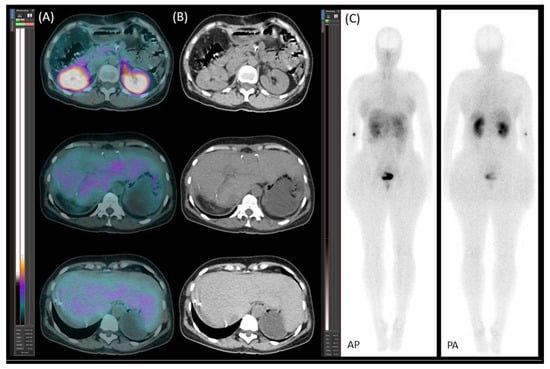

Control segmental liver function was assessed using [99mTc]Tc-mebrofenin SPECT/CT (Figure 4). The imaging confirmed adequate hypertrophy of the future liver remnant (FLR), with the following values: FLR volume fraction (FLR-V%) at 46%, FLR functional volume fraction (FLR-FV%) at 66%, and FLR filtration rate at 3.16%/min/m2.

Figure 4. [99mTc]Tc-mebrofenin SPECT/CT after parenchymal modulation. (A) Transaxial SPECT/CT and (B) native low-dose CT images show the distribution of functional hepatocytes, highlighting the dominance of the hypertrophied left lobe. The right lobe metastases appear as photopenic hypodense areas (marked with stars), with the arrow indicating the right portal vein ligation.